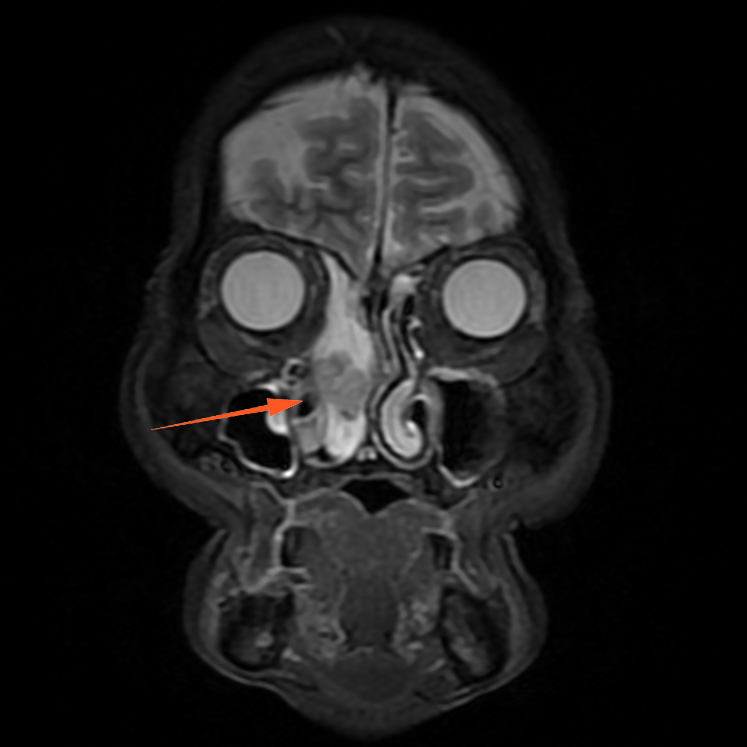

进一步增强MR显示:鼻腔右侧异常信号影,T1等信号,T2等高信号,DWI高信号,增强后周边强化为主。

蒋主任仔细阅读影像学图像,该患者的肿物在T2相有 “脑回征”,但又不典型,鼻窦骨质也没有明显的增生,肿物已经占满整个右侧额窦窦腔,好在患者额窦气化尚可,肿物未越过瞳孔中线,要彻底清除肿物,需要打开额窦,将窦内软组织完全清理干净并磨除基底部部分骨质再烧灼。